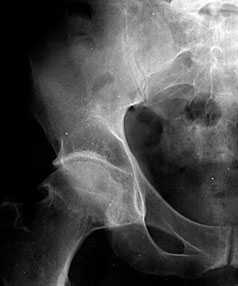

В начальных стадиях (1-2 стадии по Kellgren) ОА тазобедренных суставов при рентгенологическом исследовании определяются: незначительное сужение суставной щели, слабовыраженный субхондральный остеосклероз, точечные кальцификаты в области наружного края крыши вертлужной впадины (зачаток остеофитов), заострение краев ямки бедренной головки в области прикрепления круглой связки бедренной головки (рис. 1).

Рис. 1. Обзорная Rо-графия тазобедренного сустава в прямой проекции.

Деформирующий остеоартроз II ст. по Kollgren. Крупные остеофиты на краях суставных поверхностей. Грибовидная деформация бедренной головки